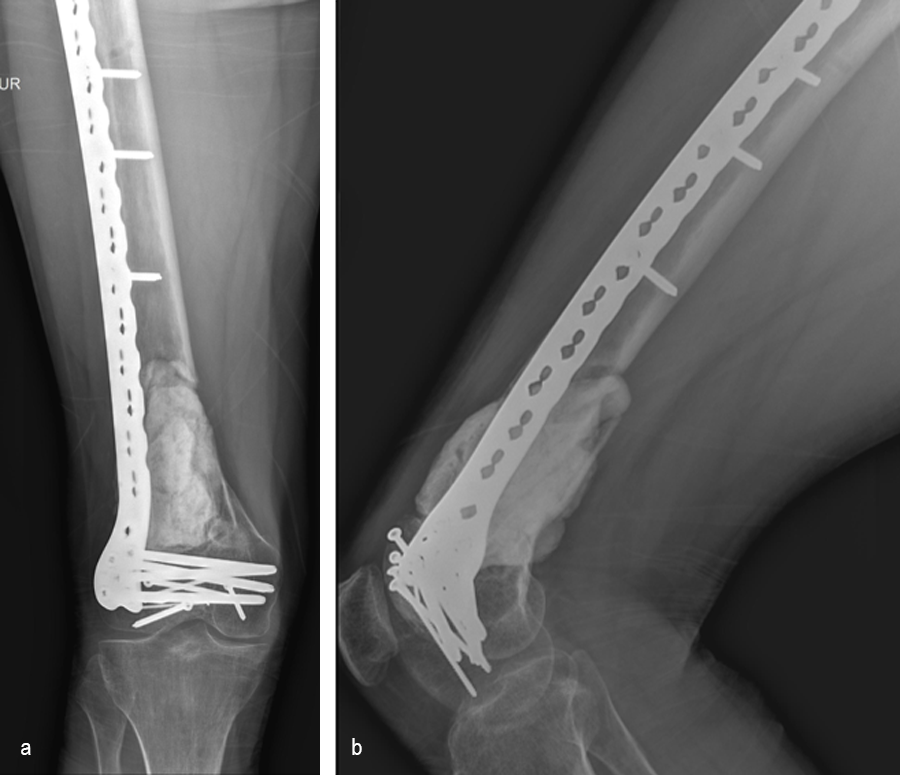

Following the advent of Covid-19 in early 2020, the patient was lost to follow-up for almost one year and was eventually seen again in December 2020 (Fig 8). At this follow-up, a CT scan was planned for the right distal femur and a graft cage ordered. Surgery was scheduled for early 2021.

At the 3-week follow-up (post-graft cage, Fig 12), the patient’s wounds were healthy. He had a range of motion (ROM) of 0–80 in his right knee. He was allowed weight bearing as tolerated (WBAT) with crutches.

At the 3-month follow-up (Fig 13), the patient had a ROM of 0–120 in his right knee. His quadricep muscles had significantly recovered and he was able to WBAT with support from a cane.

At the 6-month follow-up (Fig 14), the patient was able to WBAT on the right lower extremity. He had some ankle pain and a ROM of 0–125 in his right knee. The patient was able to walk without any assistance device.